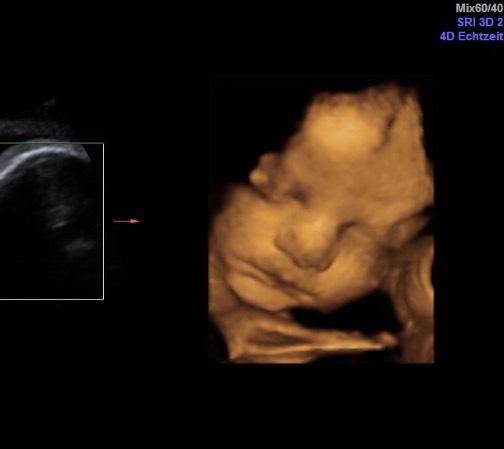

mega süß wir hatten am Dienstag den letzten großen US und haben auch so ein tolles Bild von unserer Charlotte bekommen häng es mal im kommi an schätz gewicht lag bei 2140g und 42 cm

Bild zu